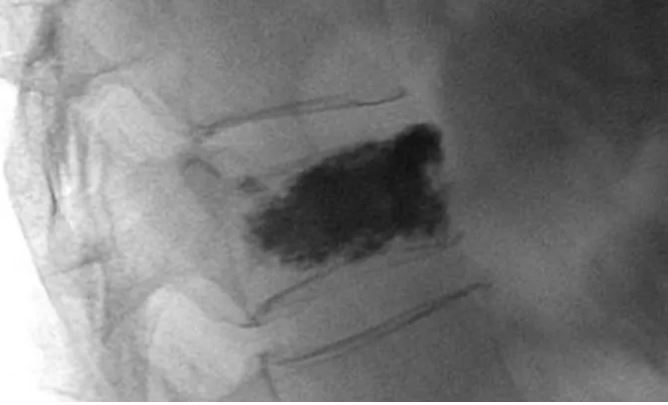

Vertebroplasti işlemi sırasında, lokal anestezi altında ve radyolojik kontrol ile, hasara uğramış olan omurga kemiği içerisine polimetilakrilat adlı kimyasal madde (kemik çimentosu) enjeksiyonu yapılır ve kemik sağlam hale getirilir. Hasta aynı gün yada ertesi gün taburcu edilir.

Omurga Kırıkları Tedavi Görüntüleri